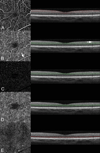

Purpose: To describe image artifacts of optical coherence tomography (OCT) angiography and their underlying causative mechanisms. To establish a common vocabulary for the artifacts observed.

Methods: The methods by which OCT angiography images are acquired, generated, and displayed are reviewed as are the mechanisms by which each or all of these methods can produce extraneous image information. A common set of terminology is proposed and used.

Results: Optical coherence tomography angiography uses motion contrast to image blood flow and thereby images the vasculature without the need for a contrast agent. Artifacts are very common and can arise from the OCT image acquisition, intrinsic characteristics of the eye, eye motion, image processing, and display strategies. Optical coherence tomography image acquisition for angiography takes more time than simple structural scans and necessitates trade-offs in flow resolution, scan quality, and speed. An important set of artifacts are projection artifacts in which images of blood vessels seem at erroneous locations. Image processing used for OCT angiography can alter vascular appearance through segmentation defects, and because of image display strategies can give false impressions of the density and location of vessels. Eye motion leads to discontinuities in displayed data. Optical coherence tomography angiography artifacts can be detected by interactive evaluation of the images.